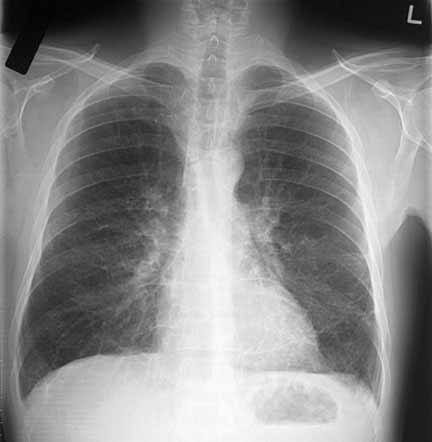

При рентгенобследовании специфических проявлений бронхита не выявляется, однако может быть усиление легочного рисунка. Рентгенологическое обследование обязательно назначается пациентом с длительным кашлем, в случае отсутствия данных о прохождении флюорографии в течение последних 2-х лет.